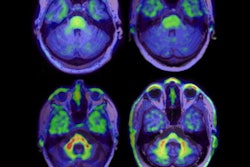

Advanced imaging can help illuminate the mechanisms of cardiovascular disease through characterizing myocardial tissue, assessing the heart's anatomy, and evaluating the presence of myocardial or vascular inflammation, the team explained. To this end, lead author Dr. Jonathan Hudson of King's College London conducted a literature review that included 45 imaging studies in 5,218 people living with HIV and 2,414 people without it.

Of these studies, 16 evaluated coronary CT angiography (CCTA), 16 evaluated cardiac MRI, 10 evaluated vascular PET, and three evaluated both CCTA and vascular PET exams. Primary outcomes were CCTA-defined moderate to severe (≥ 50%) coronary stenosis; cardiac MRI-identified myocardial fibrosis revealed by late gadolinium enhancement; and PET-defined vascular and myocardial target to background ratio.

The studies showed that on imaging, people with HIV had higher prevalence of moderate to severe coronary disease and myocardial fibrosis compared to those without HIV.